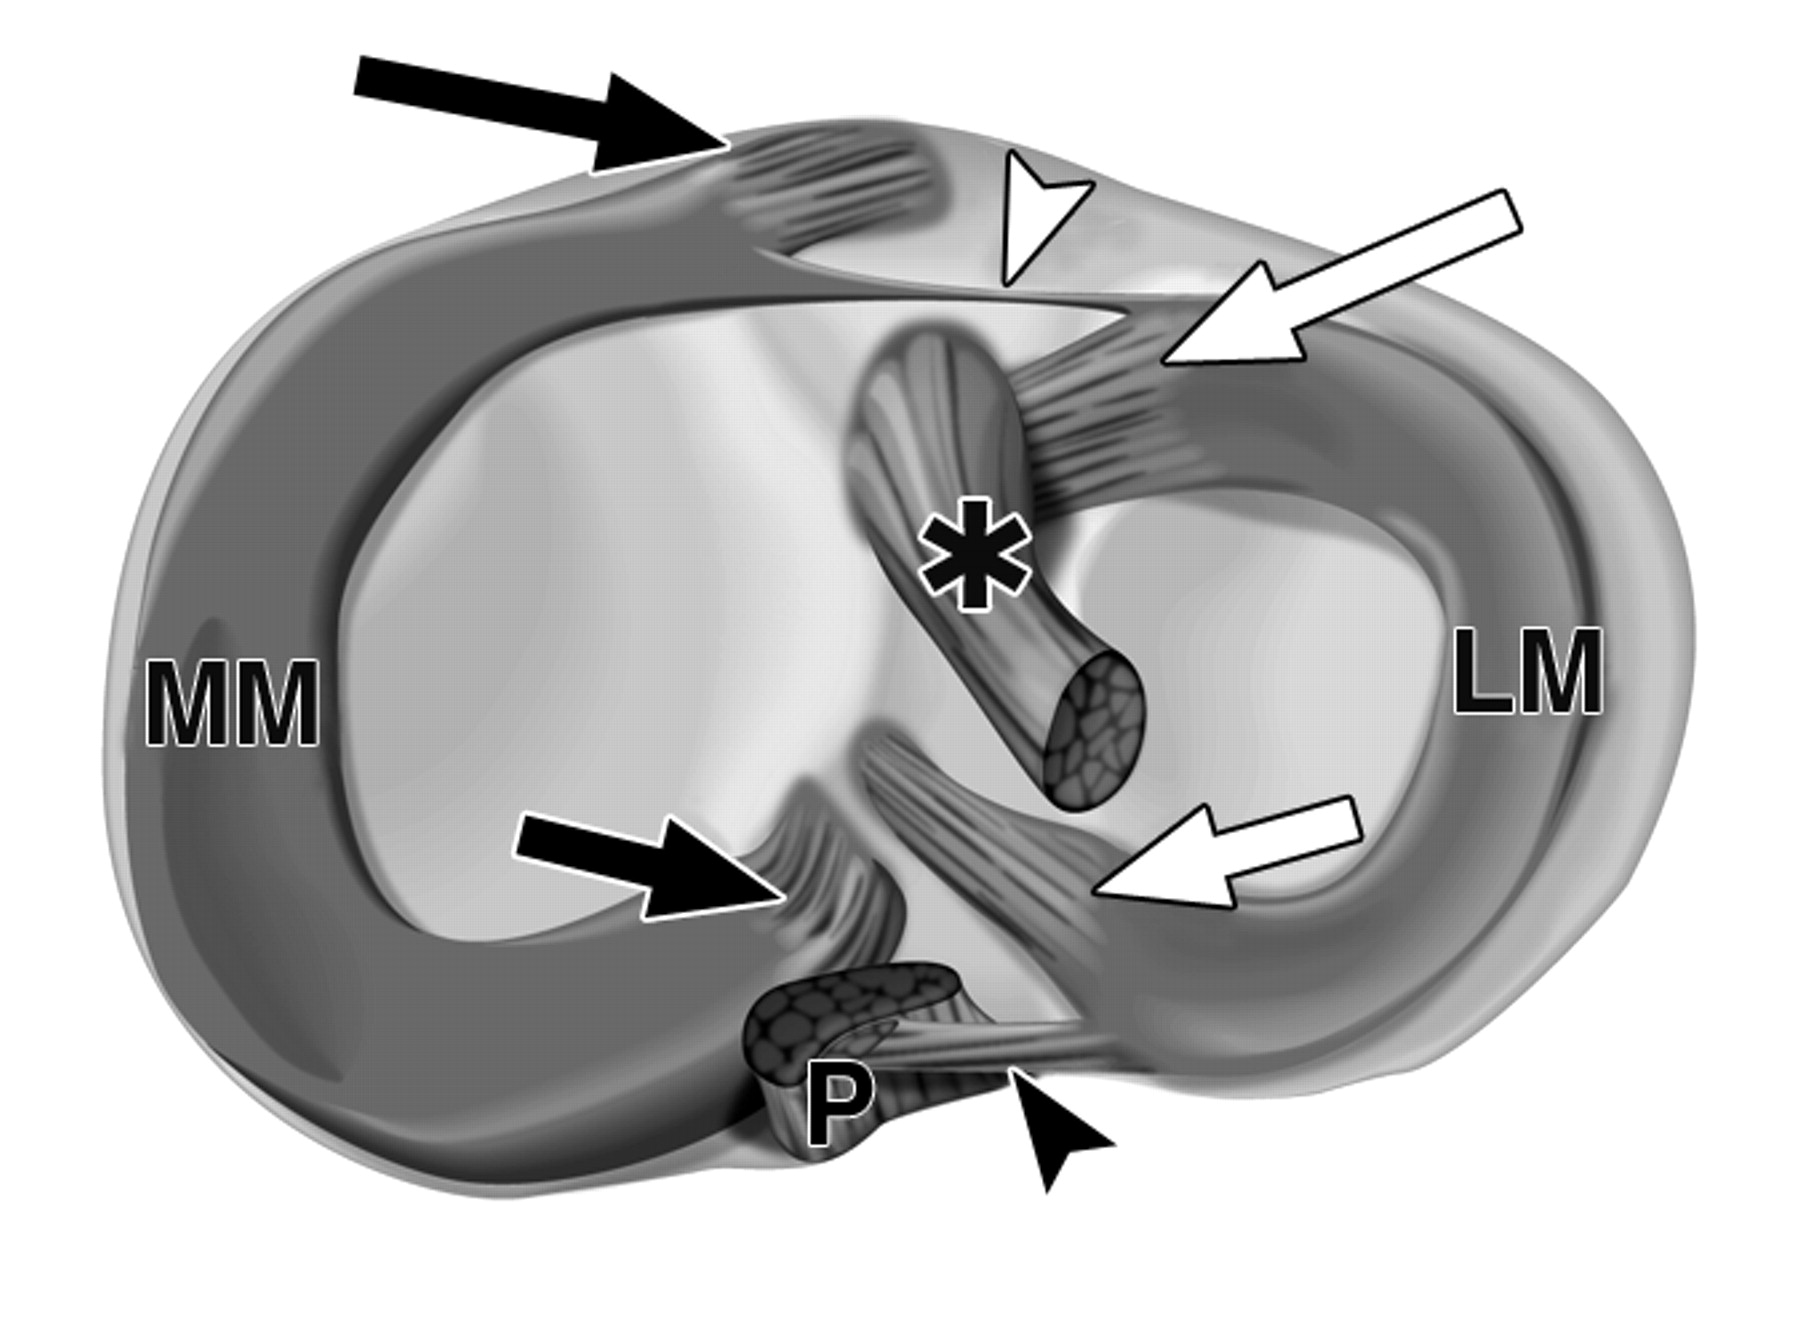

图1A-59岁男性。

黑色长箭头表示内侧半月板(MM)前根;黑色短箭头表示内侧半月板后根;白色长箭头表示外侧半月板(LM)前根;白色短箭头表示外侧半月板后根。上视图显示了右侧胫骨关节面上的相对插入部位位置。